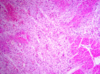

Organizing myocardial infarct

Visible changes occure after _____hrs.

The necrotic are is replaced by what?

Visible gross changes after 18 hrs

Necrotic area replaced by granulation tissue

Connective tissue, fibroblast, inflammatory cells, thin vessels

Scar maturation – more collagen